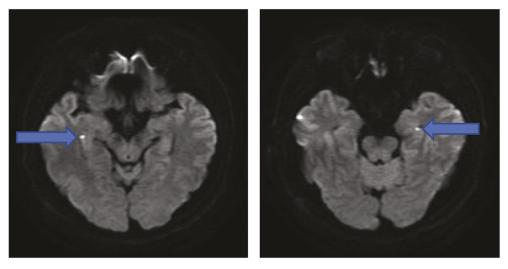

IRM montrant des hypersignaux punctiformes en séquence de diffusion à la partie latérale des hippocampes droit et gauche au cours d’un ictus amnésique.